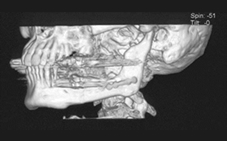

1. 血管柄付きの骨皮弁を用いた顎骨再建

口腔がんや良性腫瘍の切除後に顎骨に大きな欠損が生じ、歯が失われる場合に機能的、審美的に問題が生じます。血管柄つきの骨皮弁を用いた顎骨再建を行い、義歯やデンタルインプラントを入れることで、咬むこと、話すことに対するさらなる機能向上を目指しています。

肩甲骨皮弁による下顎骨再建例(本学顎口腔外科学講座原田教授による)

矢印内の広範に下顎骨を切除した後に、肩甲骨皮弁で再建し、移植骨にきざみを入れることで、本来の下顎骨の形態に近づけている。

顔貌の形態が良好に保たれている。

デンタルインプラントを埋入し、咬合機能の改善がはかられている。